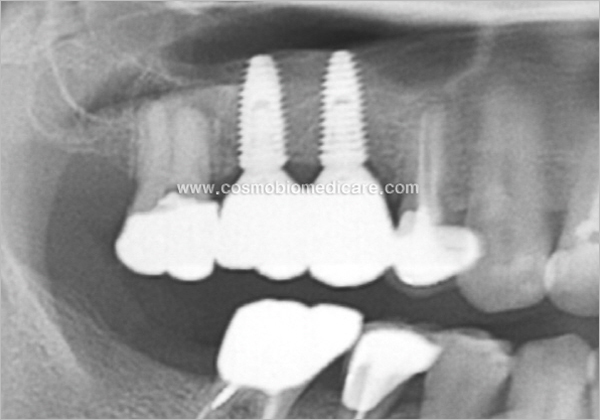

Clinical Cases

• Case1

• Case2

• Case3

• Case4

• Case5

• Case6

• Case7

• Case8

• Case9

• Case10